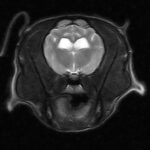

Risonanza Magnetica

Nella nostra Clinica Veterinaria è possibile effettuare la Risonanza Magnetica

Vuoi sapere come funziona una Risonanza Magnetica?? leggi l’articolo

Che differenza c’è tra TAC e Risonanza Magnetica?? leggi l’articolo